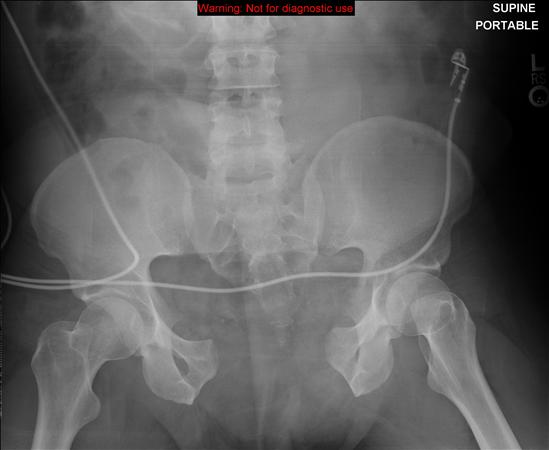

VS (vertical shear)는 hemipelvis 형태로 전이가 이뤄집니다. symphysis가 벌어지기도 하고 rami, iliac wing, sacral fx, SI jt posteriorly 모두 손상을 입게 됩니다.